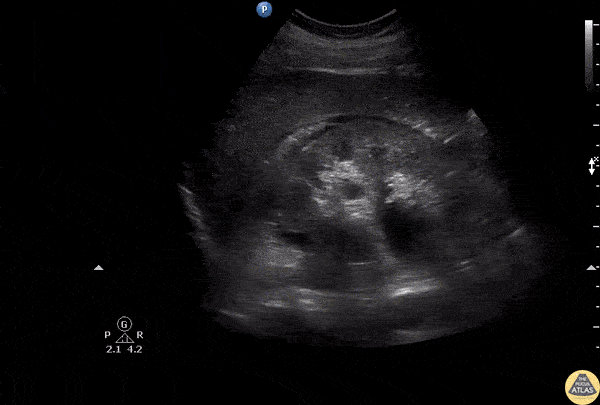

A patient presented with right flank pain. Ultrasound of the kidney revealed hydronephrosis with surrounding urinoma due to a suspected minor calyx rupture. Image courtesy of Robert Jones DO, FACEP @RJonesSonoEM Director, Emergency Ultrasound; MetroHealth Medical Center; Professor, Case Western Reserve Medical School, Cleveland, OH View his original post here